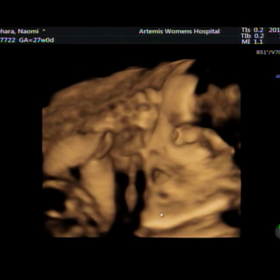

27w 妊婦検診 3D、4Dエコー&料理教室